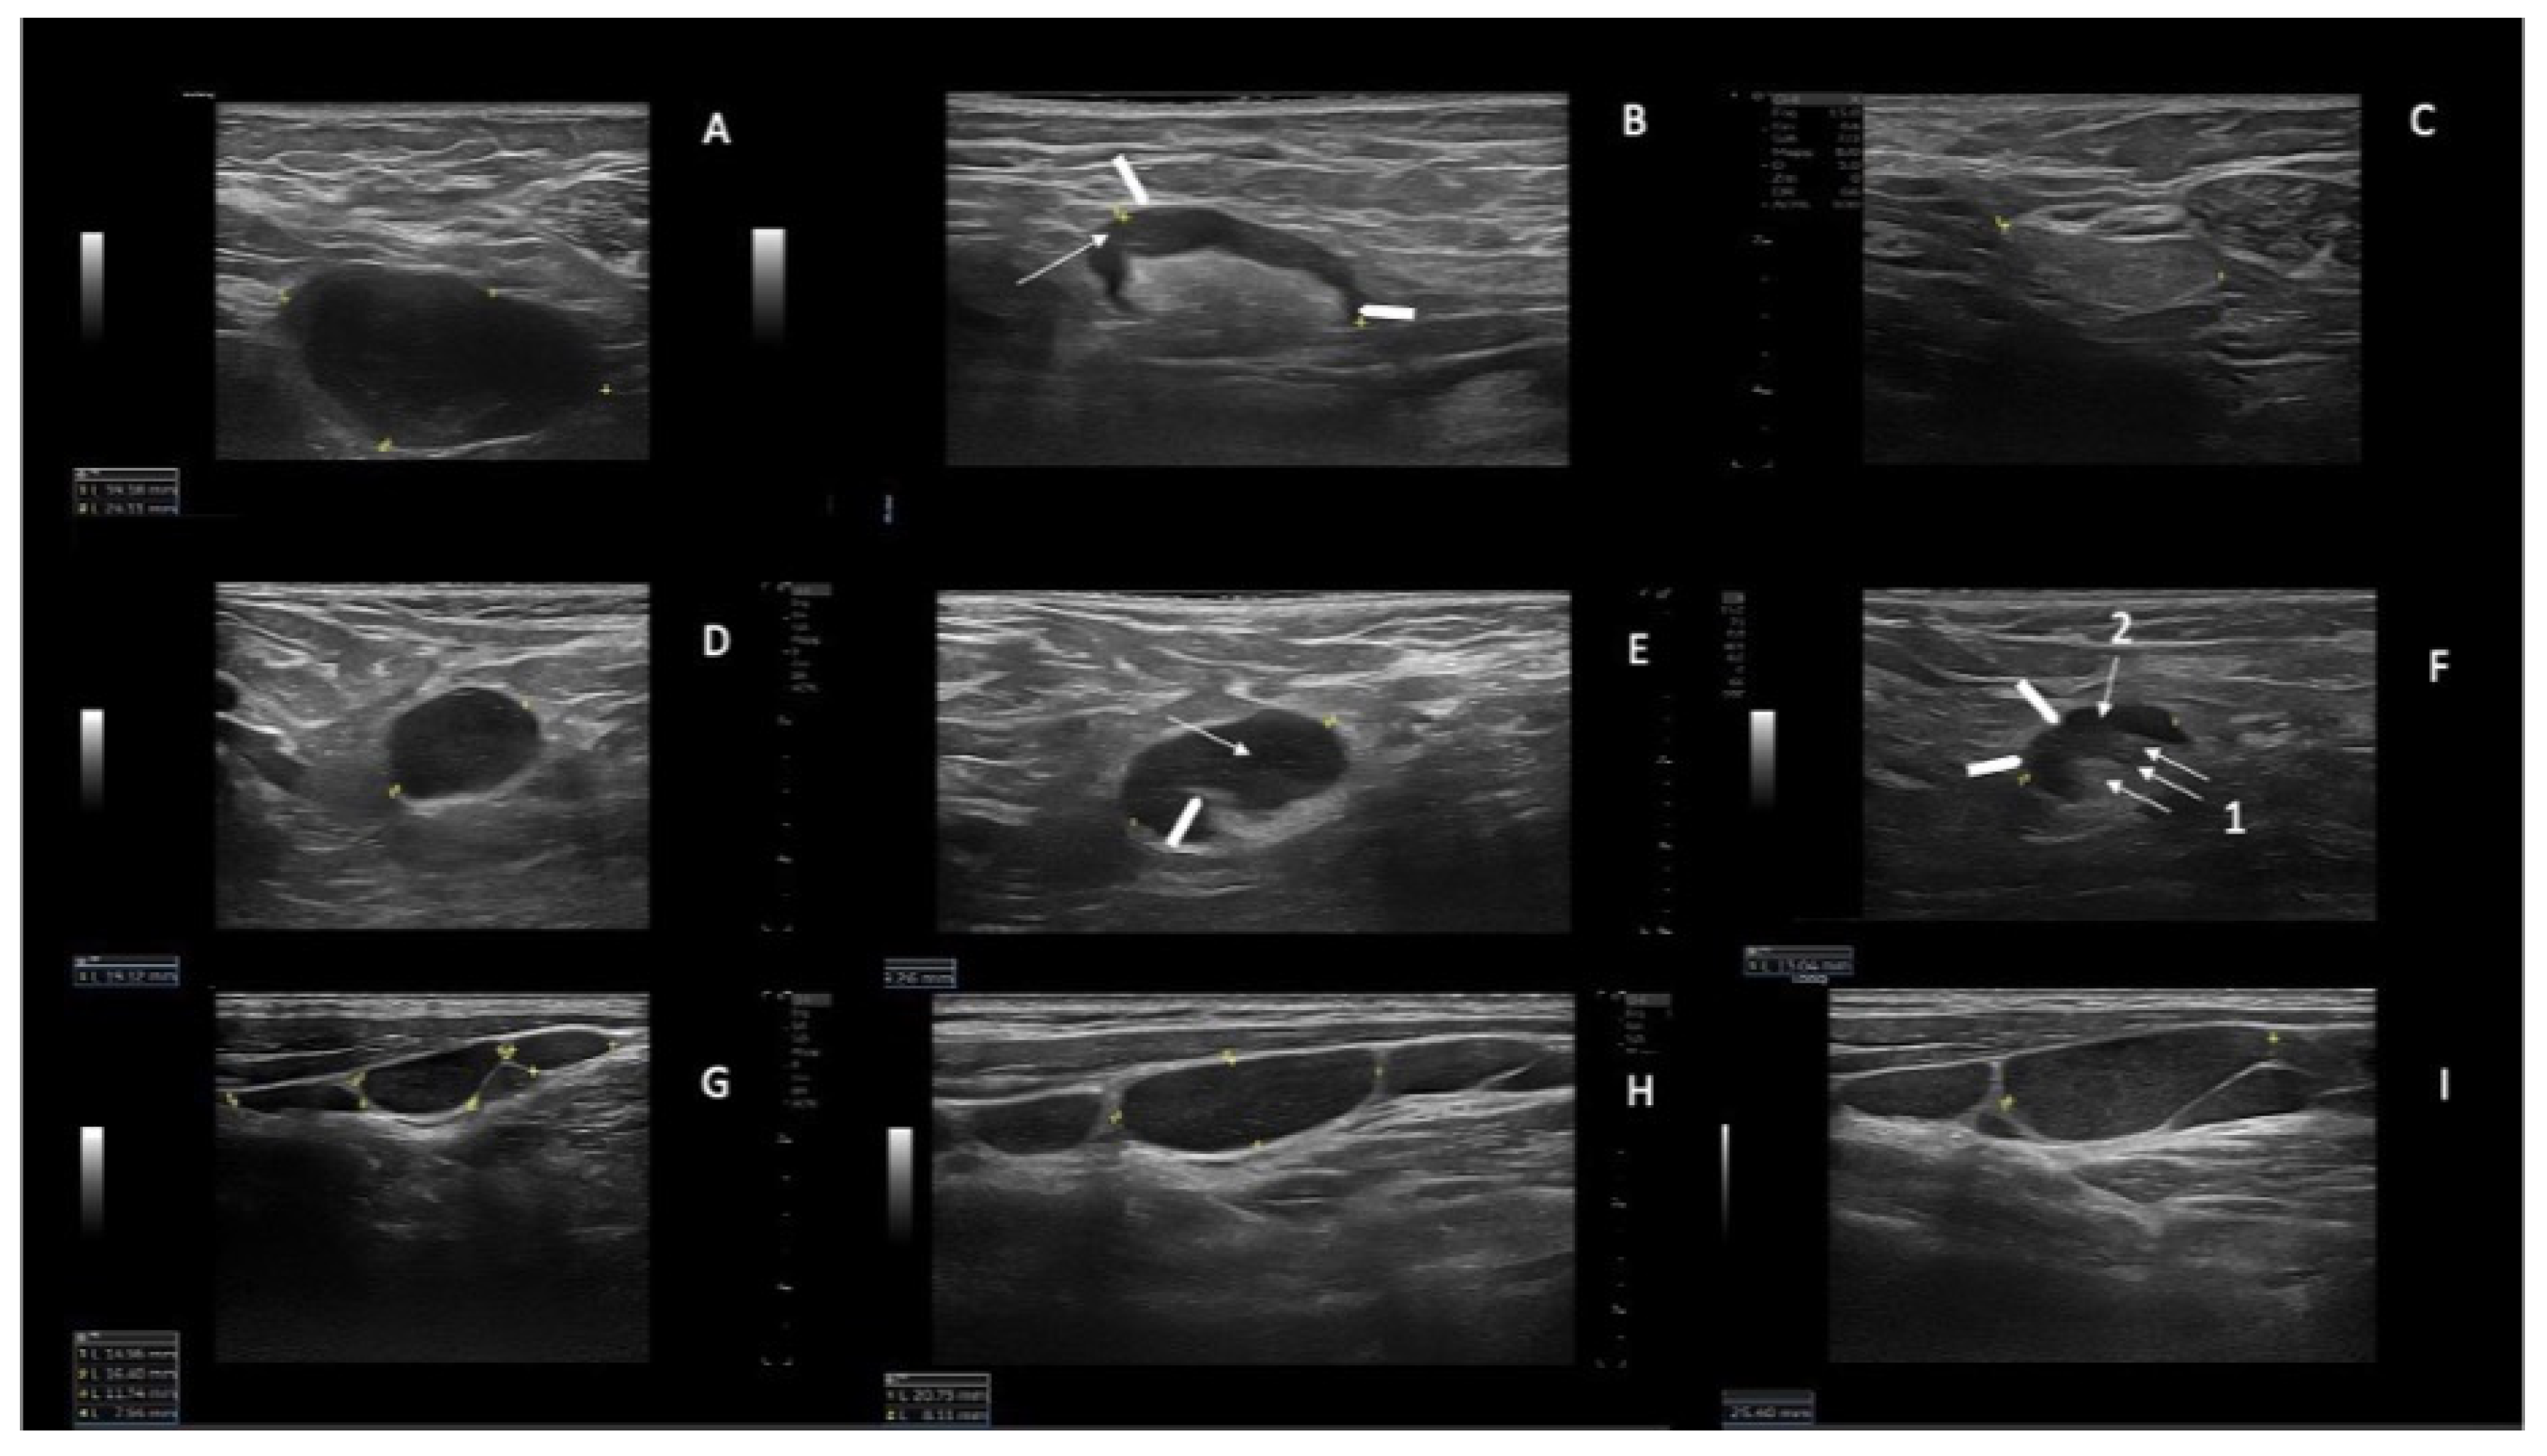

Examples of SupLNs achieving CR, SupLNs in persistent PR, and SupLN in SD. (A) Right axillary CLL-LN (39 mm × 24 mm) at baseline (T0). The LN appears hypoechoic, with sharp and regular borders, without a visible hilum, L/S ratio < 2, and with a thickened and reticulated cortex. (B) the same LN at T3 (27.3 mm) showing a partial involvement by CLL. The cortex appears inhomogeneous (the anterior part more thickened than the posterior part-white arrowheads, with reticulated cortex-white arrow). The hyperechoic hilum is visible, although irregular. (C) the same LN measuring 19.3 mm, has become liposclerotic (nodal CR) at T6. (D) Right axillary CLL-LN (19 mm) at T0, with round shape (L/S < 2) showing the same US features as for the LN shown in panel A. (E) the same LN at T6 showing a partial involvement by CLL (19.2 mm): US show a visible hilum which is displaced and truncated (white arrowhead 1), the cortex is thickened inhomogeneous, with reticulation (white arrow). (F) the same LN at T15 (13 mm) showing a persistent partial CLL involvement of the LN: the cortex is still not homogeneously thickened, which determines irregular borders of the LN (white arrowheads) and irregular shape of the hilum (white arrow 1) which appears dislocated in the posterior part of the LN. The cortex shows reticulation (white arrow 2). (G) left laterocervical CLL-LN in SD at T0. (H) left laterocervical CLL-LN in SD at T12. (I) Left laterocervical CLL-LN in SD at T24. The SupLNs present “chain”-shaped, contiguous, sharp borders without US visible hilum. The cortex is inhomogeneous and thickened, with reticulation.

Using a high resolution US linear probe, we found that in several SupLNs the echostructure showed features of involvement by CLL present only in a small portion of the LN, which was never described before. This echostructure feature was detected in N = 8 patients (36.3% of our casuistic), and in 4/8 it was a transient US status, because eventually achieved a status of US nodal CR (Figure 1A–C), and accordingly reached a PB-uMRD. Two patients out of 4, with a partial US residual involvement by CLL (Figure 1D–F and Figure 2D–G) attained uMRD.

Moreover, we report on SupLNs with echostructure consistent with a partial involvement by CLL detected with high resolution linear probe. This partial involvement of SupLNs has never been described before in patients affected by CLL. These echostructure features appear to either stabilize into a persistent PR (Figure 1D–F and Figure 2D–G) or appear a transient status turning into a complete nodal CR (Figure 1A–C). This transient change in the echostructure of SupLNs might be explained by a total of ten US examinations (1 at baseline T0, three during combination treatment and six from EoCT until the end of second year).